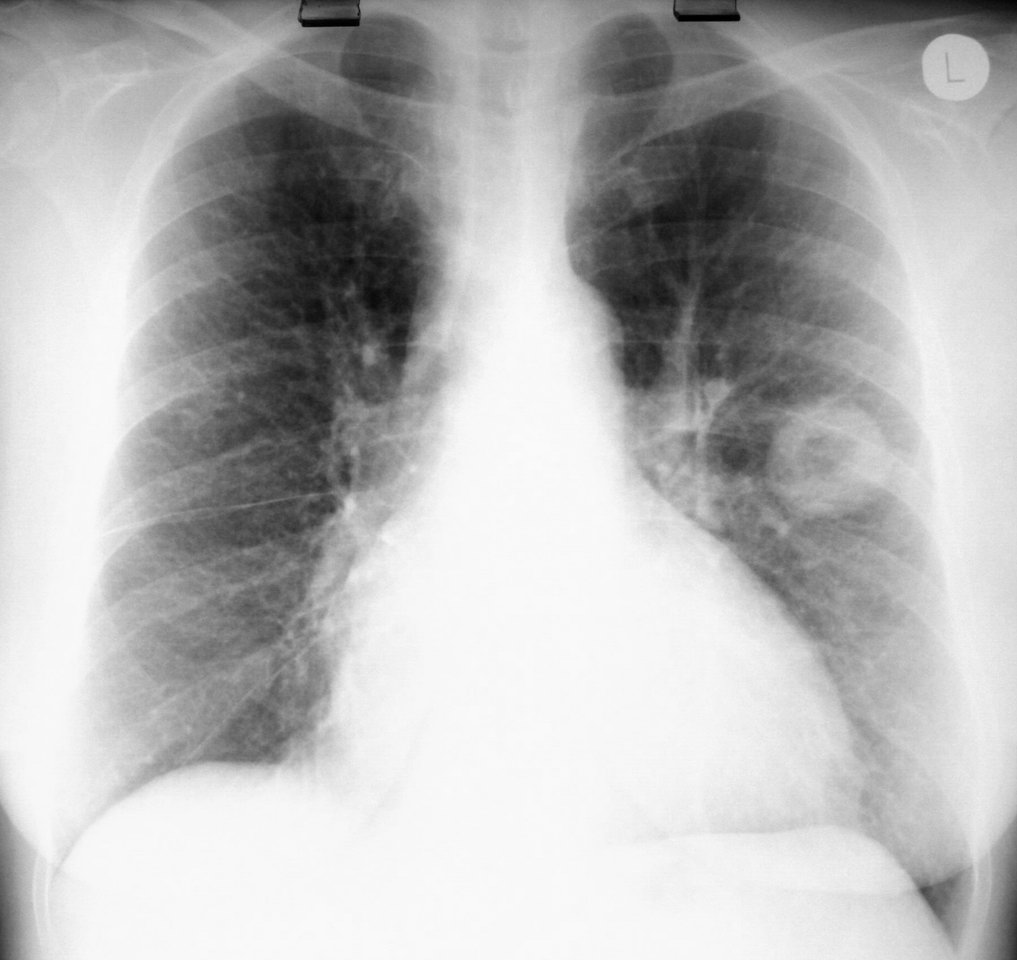

TB destroys another lung |

Examining multi-drug-resistant TB patient. Note the total lack of isolation precautions. |